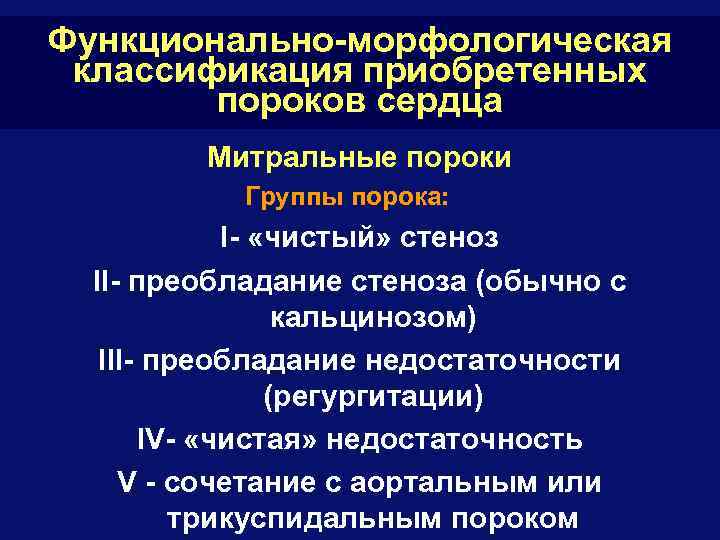

Функционально-морфологическая классификация приобретенных пороков сердца Митральные пороки Группы порока: I- «чистый» стеноз II- преобладание стеноза (обычно с кальцинозом) III- преобладание недостаточности (регургитации) IV- «чистая» недостаточность V - сочетание с аортальным или трикуспидальным пороком